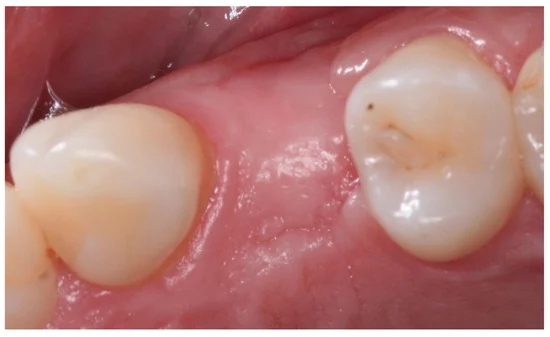

발치 1년 후 뼈가 차오른 사진

적절한 시기에 회복하지 않아 뼈가 퇴화한 사진

사진에서 보듯 발치 한 부위를 비워둔지가 오래 되어서

해당부위 뼈의 양이 부족하고, 반대편 치아가 정출 되었으며, 뒤 치아가 쓰러져 있음을 알 수 있습니다.